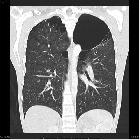

Marijuana (cannabis or bong) lung refers to the presence of large apical bullae in patients who regularly smoke marijuana. A definite causative link between smoking marijuana and bullous lung disease has not been established, and the association may just be coincidental.

Macroscopic emphysema is rarely seen although large apical bullae in a paraseptal distribution have been described with secondary spontaneous pneumothorax as a complication . A definite causal link has yet to be established .